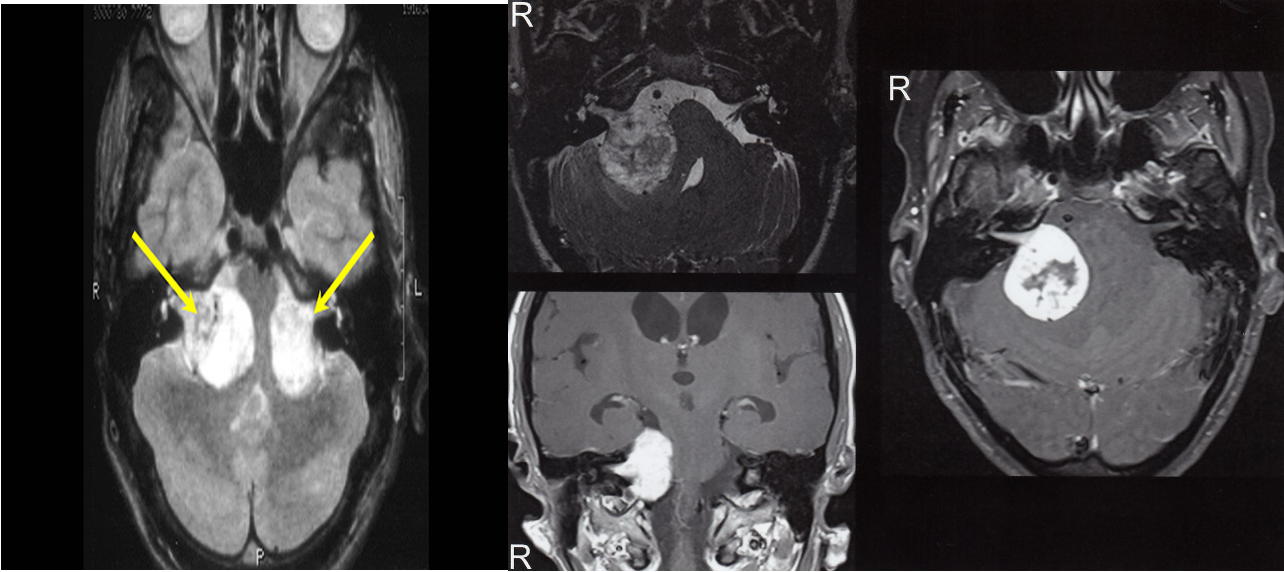

(Acoustic schwannoma, Vestibular schwannoma)

Contrast MRI (imaging modality of choice) & CT with and without contrast is an alternative for those who cannot undergo MRI.

Which show an enhancing lesion by the internal auditory canal, with possible extension into the cerebellopontine angle.

Bilateral acoustic schwannoma has a strong association with neurofibromatosis type 2

Cranial MRI, Upper left: T2-weighted image (axial view). Lower left and right: T1-weighted images after application of contrast agent (axial and coronal views). A tumor is visible on the right side between the brainstem and the cerebellum , extending into the IAC. There is strong contrast enhancement